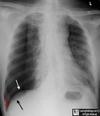

What is the red arrow indicating?

* Deep Sulcus Sign * This is an indirect indicator of a pneumothorax.